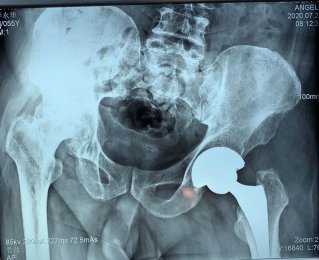

專于骨科,精于微創(chuàng)。濰坊市市立醫(yī)院骨二科以骨科微創(chuàng)為主要特色,致力于用最小的創(chuàng)傷治療疾患,并結合ERAS理念,創(chuàng)建無痛手術、無痛病房,給予患者最快最佳的術后恢復。科室開展髖膝關節(jié)疾病的個體化治療,充 分評估患者髖膝關節(jié)功能,從采用不同的 手術方案治療髖膝關節(jié)疼痛; 開展 微創(chuàng)經(jīng)皮椎弓根螺釘內(nèi)固定術、經(jīng)皮椎體成形術(PVP、PKP)術、MIPPO技術等各種骨科...[全文閱讀]

今年60歲的考大姨,飽受膝關節(jié)疼痛之苦長達8年,她曾四處求醫(yī),接受各種保守治療,至今跛行,且癥狀逐年加劇。近日因右膝疼痛加劇、腫脹,行走200米便無法繼續(xù)行走,嚴重影響日常生活,被親友急送濰坊市市立醫(yī)院治療。 骨二科主任許冬雷為患者做了詳細檢查,經(jīng)醫(yī)生…【查看詳細】